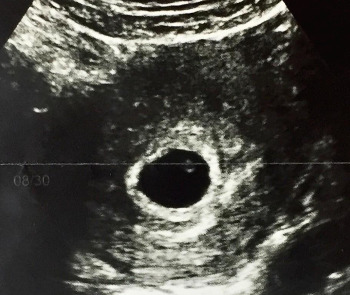

보통 6주 이후부터 심음이 확인되며, 6-12주 사이의 CRL 길이를 기준으로 임신주수를 정하게 됩니다.

✅ 머리 엉덩 길이 (Crown-Rump Length) : 임신 1분기 아기의 크기를 재는 기준이 됩니다.

아기집 (Gestational Sac, GS)으로도 주수를 추정할 수 있지만 CRL을 사용하는 경향이 있습니다.

USG2.jpg 아기의 형태가 약간 보이긴 하나, 손가락 발가락 구별할 정도는 안됩니다.CRL을 측정할 수 있습니다.